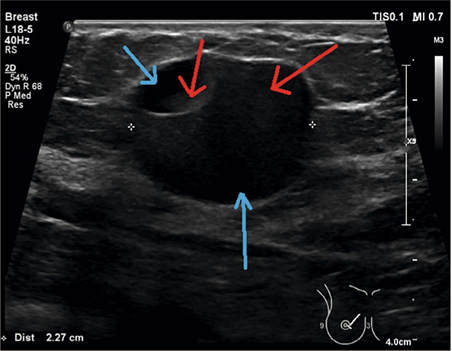

Een maand later is de zwelling nog steeds niet weg. Bij onderzoek palpeert haar huisarts nu een gladde, vrij te mobiliseren, niet drukpijnlijk zwelling, zonder tekenen van infectie en vermoedelijk enige fluctuatie. Uit echografie blijkt dat de patiënte een uit 2 delen bestaande cyste heeft: een deel bestaat uit vet/melk [figuur, rode pijlen] en het andere deel uit water (blauwe pijlen). Haar huisarts concludeert dat het om een galactocele gaat. Via een punctie wordt een melkachtige substantie geaspireerd. Ze merkt direct verlichting. Na een maand is ze klachtenvrij.

Figuur | Echobeeld van een galactocele. De rode pijlen wijzen een hogere dichtheid/reflectie aan, dus vet/melk. De blauwe pijlen wijzen waterscheiding/-verdeling aan.

Echobeeld van een galactocele. De rode pijlen wijzen een hogere dichtheid/reflectie aan, dus vet/melk. De blauwe pijlen wijzen waterscheiding/-verdeling aan.